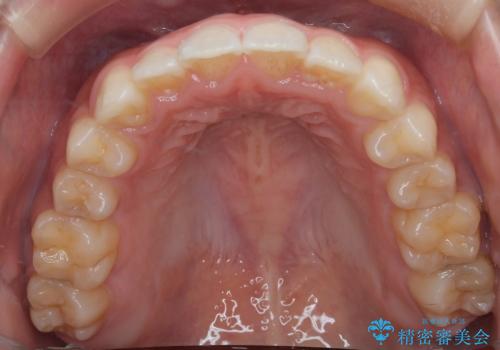

- 前歯の叢生を主訴に来院されました。非抜歯でインビザラインで治療をしました。

叢生はIPRをし、並べました。この患者様はオープンバイトだったため歯を並べる過程でかみ合わせも治しました。